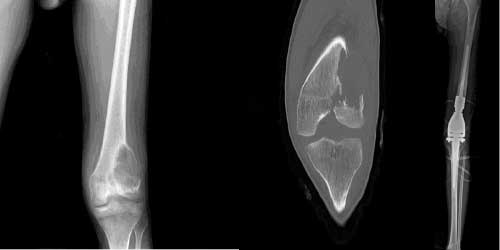

Her ameliyatın olduğu gibi kemik ve yumuşak doku tümör ameliyatlarının da riskleri vardır. Bu riskleri genel ve yapılan ameliyata özgü olmak üzere kabaca iki başlık halinde gruplandırabiliriz. Öncelikle anestezi ile ilgili risklerin anestezi uzmanı tarafından (...)

Ameliyat sonrası takip ve kontrol hastanın ameliyat masasında uyanması ile başlar. Özellikle damar ve veya siniri ilgilendiren ameliyatlarda hasta ameliyat masasından alınmadan ekstremitenin dolaşımı ve ilgili sinirin fonksiyonu kontrol edilir.